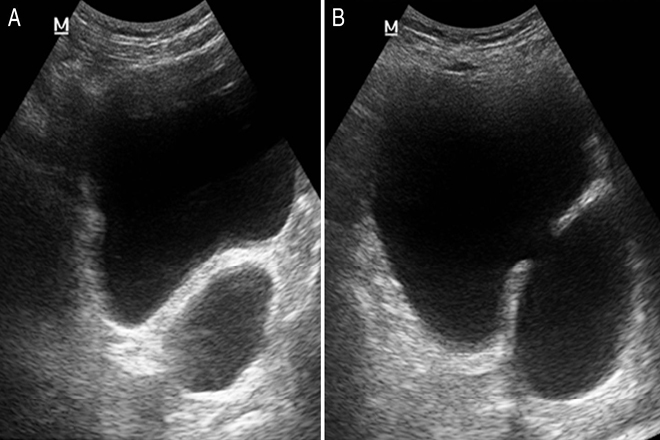

Este algoritmo fue comparado con un GOLD STANDARD: el diagnóstico definitivo de HPB tras evaluación del sedimento urinario, volumen miccional residual, tamaño prostático por ecografía y flujometría urinaria.